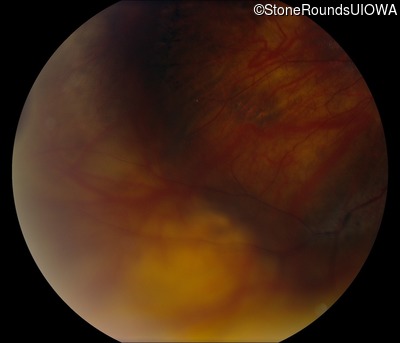

Fundus Photography - Right - 20/60 -2

Exemplar